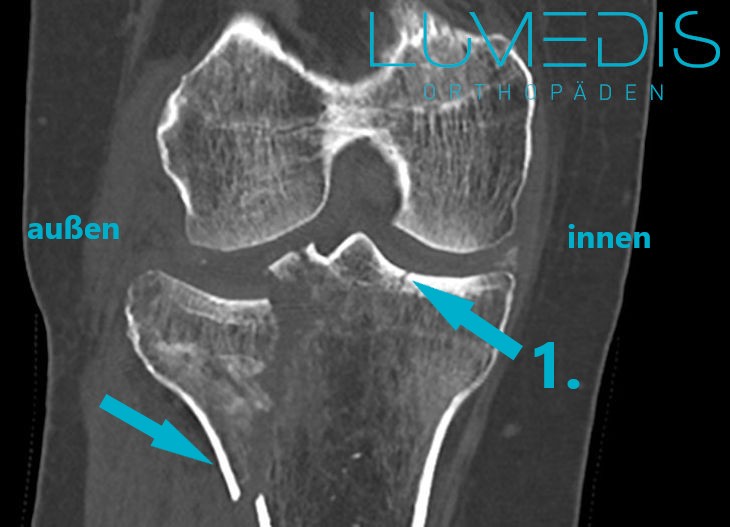

CT-Rekonstruktion einer Tibiakopffraktur links

CT einer rechten lateralen Tibiakopffraktur

Die Pfeile zeigen auf die verschiedenen Frakturlinien im Tibiakopf.